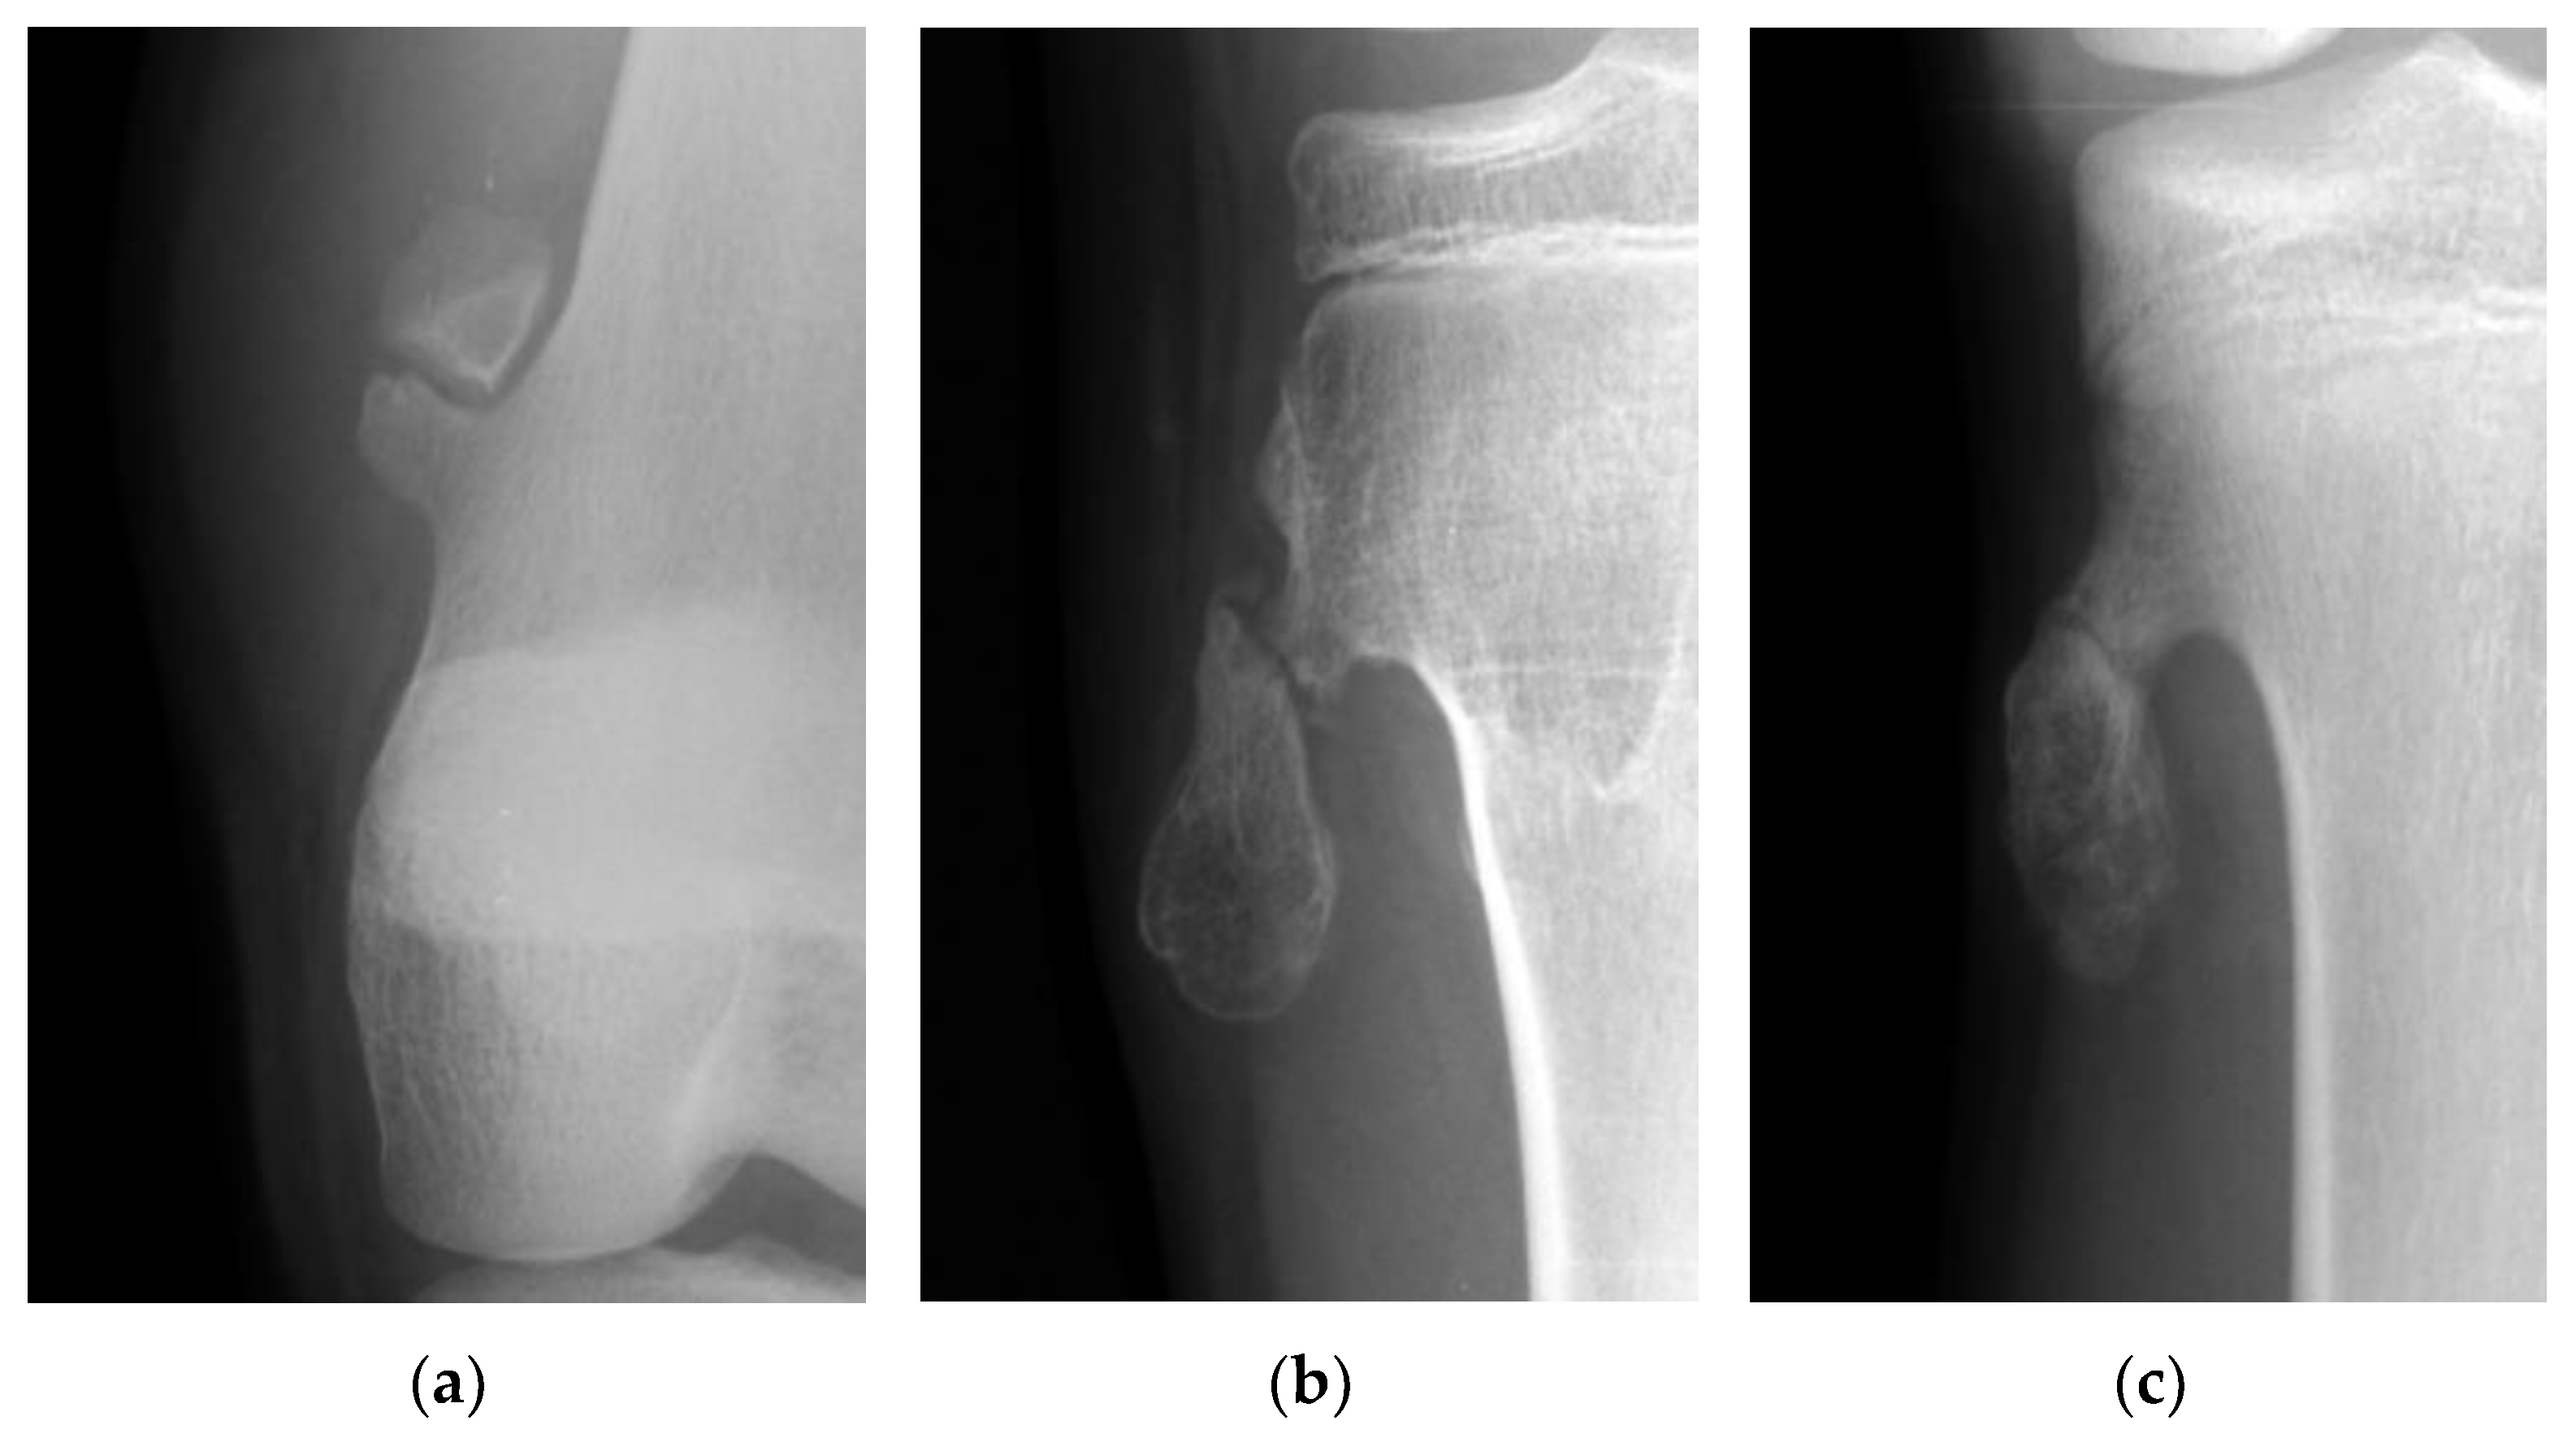

The fractures of the osteochondromas were divided into two types: displacement and non-displacement. In the present study, displacement was defined as a gap widening of more than 1 mm between fragments, or translation of more than 50% of the distal fragment in relation to the proximal fragment, either by anteroposterior, lateral, or oblique radiographic views of the knee joint (Figure 1). There were 12 patients in the displacement group and 11 patients in the non-displacement group (Figure 2).

Figure 2.

(a) The picture shows a gap widening of more than 1 mm between fragments of an osteochondroma in the femur. (b) The picture shows a more than 50% translation of a fractured osteochondroma in the tibia. (c) The picture shows a fractured osteochondroma in the tibia from the non-displacement group.